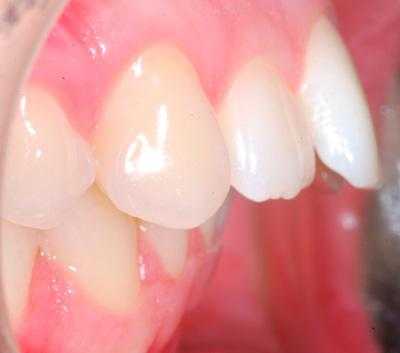

В полости рта дистальный прикус определяется по выступающим вперед верхним фронтальным зубам. В норме, при ортогнатическом прикусе, верхние резцы перекрывают нижние примерно на 1/3. При дистальной патологии между верхними и нижними резцами образуется расстояние — «саггитальная щель».

- I подкласс — верхние резцы направлены вперед, иногда немного вверх. Для этого вида дистальной окклюзии характерная саггитальная щель.

Определяющими внутриротовыми признаками дистального прикуса служат выдвижение вперед верхних фронтальных зубов; несмыкание верхних и нижних резцов с наличием между ними сагиттальной щели; нарушение взаимного расположения боковых зубов в переднезаднем направлении. В чистом виде дистальный прикус встречается редко; гораздо чаще он сочетается с аномалиями положения зубов, диастемой, тремами, глубоким, открытым или перекрестным прикусом, готическим нёбом.